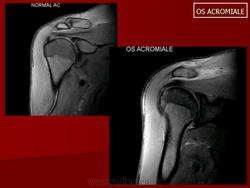

МРТ.  Os Acromiale